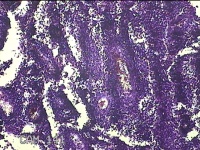

右腋下结节

性别

男

年龄

37岁

临床诊断

腋窝乳糜囊肿

一般病史

发现右腋下结节1年余,近日出现局部红肿及疼痛。

标本名称

大体所见

灰白暗红色组织2.7x1.8x0.8cm一块,表面带梭形皮肤2.8x1.3cm,皮下见结节2.7x1.3cm一个,切开结节呈实性,切面灰白粉红色,质软。

图1

慢性脓肿

皮肤慢性炎症伴局灶性化脓性炎症。

所提供图片不具有诊断价值,炎性病变可能。